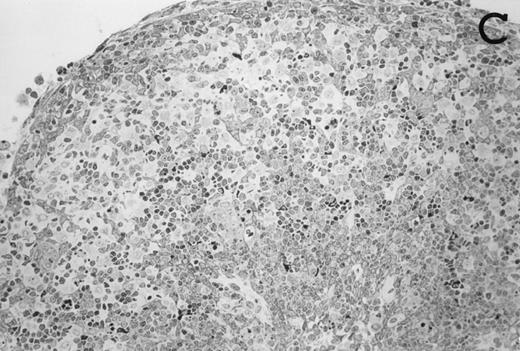

Accordingly, the DN cell subset seemed to include a large number of nonlymphoid cells after 12 days of treatment with IL-7. A histological and ultrastructural study of IL-7–treated and control FTOC was then performed to confirm the nature of these cells. A peripheral band of pale cells, morphologically identifiable as DC, was clearly present in IL-7–treated lobes (Fig 3). In contrast, thymocytes largely predominated in control FTOC (Fig 3). The ultrastructural analysis confirmed the existence of a large number of mature DC in IL-7–treated cultures. They were large, irregular, electron-lucent elements, with lobulated nuclei and cytoplasmic organelles arranged close to the nucleus (Fig4A). Moreover, immature DC, which had shorter cell processes, a less irregular nucleus, and few membranous organelles scattered throughout the cytoplasm, were also observed in these lobes (Fig 4B).

Large numbers of DC develop in the presence of IL-7. Thymic lobes were organ-cultured under control conditions (original magnifications: A, 130×; B, 650×) or in the presence of IL-7 (original magnifications: C, 130×; D, 650×) for 12 days. Note the peripheral band of pale cells in IL-7–treated lobes (C). These cells mostly correspond to DC (asterisks; D). In contrast, thymocytes (arrows) predominate in control lobes (B).